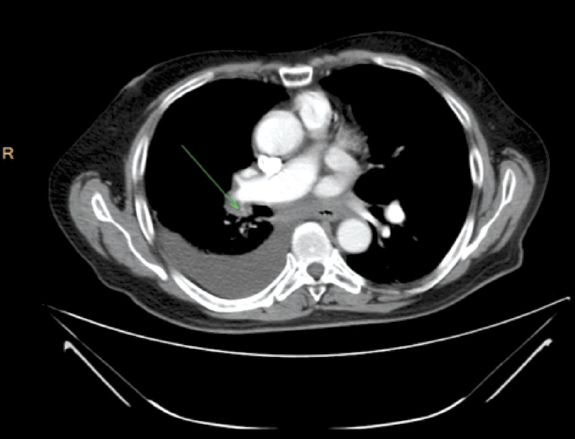

Ответ на терапию оценивался по данным мультиспиральной компьютерной томографии (МСКТ) по двум таргетным очагам: образование в корне правого легкого размерами 93×85×119 мм (очаг №1), конгломерат увеличенных внутригрудных лимфоузлов размерами 65×72×118 мм (очаг №2); рис. 1.

Рис. 1. Пациент 1934 г. р. МСКТ органов грудной клетки с внутривенным контрастированием, сентябрь 2017 г. (до начала лечения).

Fig. 1. The patient, born 1934. MSCT of the chest cavity with contrast, September 2017 (before the treatment).